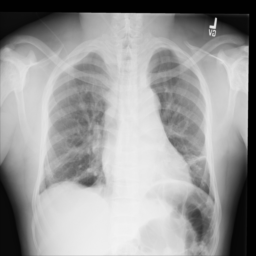

Figure 2: Examples of normal vs. abnormal images of considered datasets. Natural images: (first row) cars vs other classes of CIFAR10 dataset [1], (second row) digits “0” vs digits “1” – “9” of SVHN dataset [2]. Medical images: (third row) healthy tissue vs. tissue with metastases in H&E-stained lymph nodes images from Camelyon16 challenge [3], (fourth row) normal chest X-rays vs. chest X-rays with abnormal findings from NIH dataset [4].

Anomaly detection is a crucial task in the deployment of machine learning models, where knowing the “normal” data samples should help spot the “abnormal” ones [5, 6]. If an input deviates from the training data substantially (e.g., the input belongs to a class not represented in the training data), it is usually impossible to predict how the model will behave [7, 8]. This trait is especially important in high-consequence applications, such as medical decision support systems, where it is especially vital to know how to recognize the anomalous data. Identification of rare occurrences is another important application where anomaly detection is useful. For example, in pathology, where labeling diverse microscopy datasets is both time-consuming and expensive, the rare types of cells and tissues require specialized expertise from the annotator [9, 10]. Forthright anomaly classification and segmentation algorithms are typically prone to mistakes either because of the lack of sufficient annotation (thousands of labeled examples needed for supervised models) or because of the lack of representative data altogether (e.g., the case of some rare pathologies). Moreover, these algorithms are affected by the need to deal with very unbalanced and apriori noisy data, frequently leading to inaccurate results (e.g., the findings on chest x-rays can be so subtle that they can lead to disagreement in the interpretation [11, 12]). Because the normal cases greatly prevail over the abnormal ones, the anomaly detection could alleviate the annotation burden by automatically pointing to the rare samples.

In recent years, deep learning techniques achieved important advances in image anomaly detection [13, 14, 15, 16, 17, 18, 19, 20, 21]. However, these efforts were primarily focused on artificial problems with distinct anomalies in natural images (e.g., outliers in images of “cars” in the CIFAR10 dataset [1], see Figure 2). The medical anomalies, however, differ from those in the natural images [15, 19, 22]. Contrary to the natural images, the anomalies in the medical domain tend to strongly resemble the normal data. For example, detection of obscure neoplasms in chest X-rays [4] and of metastases in H&E-stained lymph node images [3] manifest a blatant challenge at hand, with the anomalous tissues being barely different from the normal ones (see Figure 2). Although deep learning has proved useful for a variety of biomedical tasks [23, 24, 25, 26], only recently, a few groups started dedicating their effort to the anomaly detection problem [15, 19, 27]. However, to the best of our knowledge, a thorough comparison of the state-of-the-art (SOTA) solutions in the medical domain is still missing despite the pressing demand and the prospective clinical value.

Anomaly Detection on Chest X-Rays

Chest X-ray is one of the most common examinations for diagnosing various lung diseases. We considered the task of the recognition of fourteen findings, such as Atelectasis or Cardiomegaly, on the chest X-rays in the NIH dataset (ChestX-ray14 dataset) [4] (Figure 2). Searching abnormalities on a chest x-ray is challenging even for an experienced radiologist since abnormality may occupy only a small region of lungs, or be almost invisible. The dataset consists of 112,120 frontal-view images of 30,805 unique patients: 86523 for training, 25595 for evaluation. We split the dataset into two sub-datasets having only posteroanterior (PA) or anteroposterior (AP) projections, because organs on them look differently. We tried different preprocessing during the hyperparameter search: rescaling to 256x256, 128x128, and 64x64 and histogram equalization, central crop (3/4 of the image size) to delete “noisy” borders. We considered images without any disease marker as “normal” and used them for training. Abnormal images for hyperparameter searching comprised of the training images of the most frequent disease (‘Infiltration’) out of fourteen possibilities. We also evaluated model on subset containing “clearer” normal/abnormal cases (provided by  [22]). This subset consists of 4261 normal images for training, 849 normal and 857 abnormal images for validation, and 677 normal and 677 abnormal images for testing.

Figure 6: Examples of normal (left) and anomaly (right) images of H&E-stained lymph node of Camelyon16 challenge [3] (top) and chest X-rays of NIH dataset [4] (bottom). We also showed the predicted anomaly score by the proposed method. The higher the score, the more likely to be an anomaly. Notice how the proposed method spots even the borderline cases.